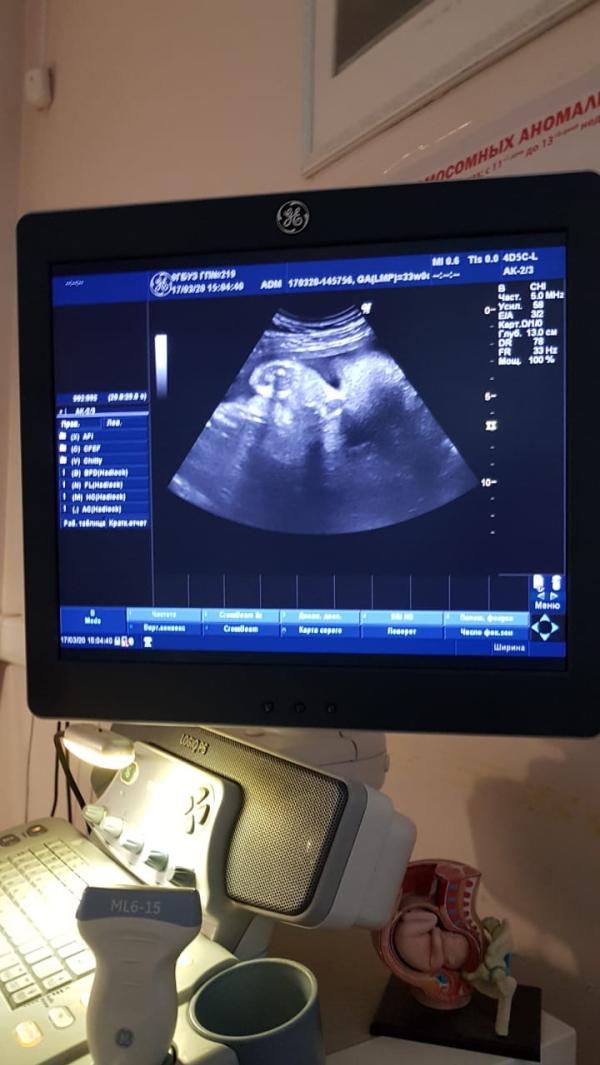

КАК ПРОХОДИТ МОЯ БЕРЕМЕННОСТЬ?🤰🏼

Я долго думала писать мне этот пост или нет, но все-таки решилась)

По началу было не понятно что со мной происходит, часто хожу в туалет (по маленькому) и тянуло дико низ живота , как при менструации , но эти дни так и не приходили , и решили сделать тест. Думали надежды напрасны, может со мной что-то не так , может застудилась?Мы долго планировали нашего сыночка, полгода попыток и вот свершилось , в конце августа тест показал ➕, радости нашей не было предела🤪